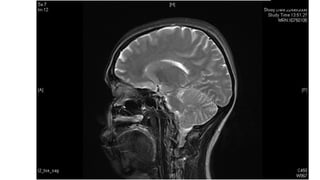

Saggital plane